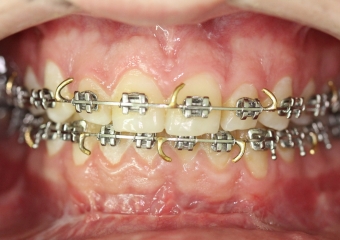

Mordida após a cirurgia